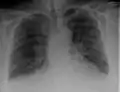

Chest X-rays are frequently used to aid in the diagnosis of CHF. In a person who is compensated, this may show cardiomegaly (visible enlargement of the heart), quantified as the cardiothoracic ratio (proportion of the heart size to the chest). In left ventricular failure, evidence may exist of vascular redistribution (upper lobe blood diversion or cephalization), Kerley lines, cuffing of the areas around the bronchi, and interstitial edema. Ultrasound of the lung may also be able to detect Kerley lines.[70]

Congestive heart failure with small bilateral effusions